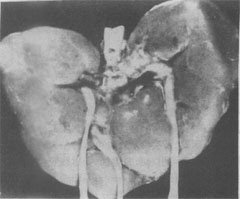

(2)Edwards综合征:染色体异常为18三体。表型特征有智力低下、小头、前额窄、枕部突、小颌且张口范围小,腭弓高窄、低位耳、肾畸形(图6-3)、肌张力增高及手紧握等(图6-4)。

三体(Edwards)综合征的畸形肾

图6-3 18三体(Edwards)综合征的畸形肾

图示马蹄状融合肾及额外输尿管